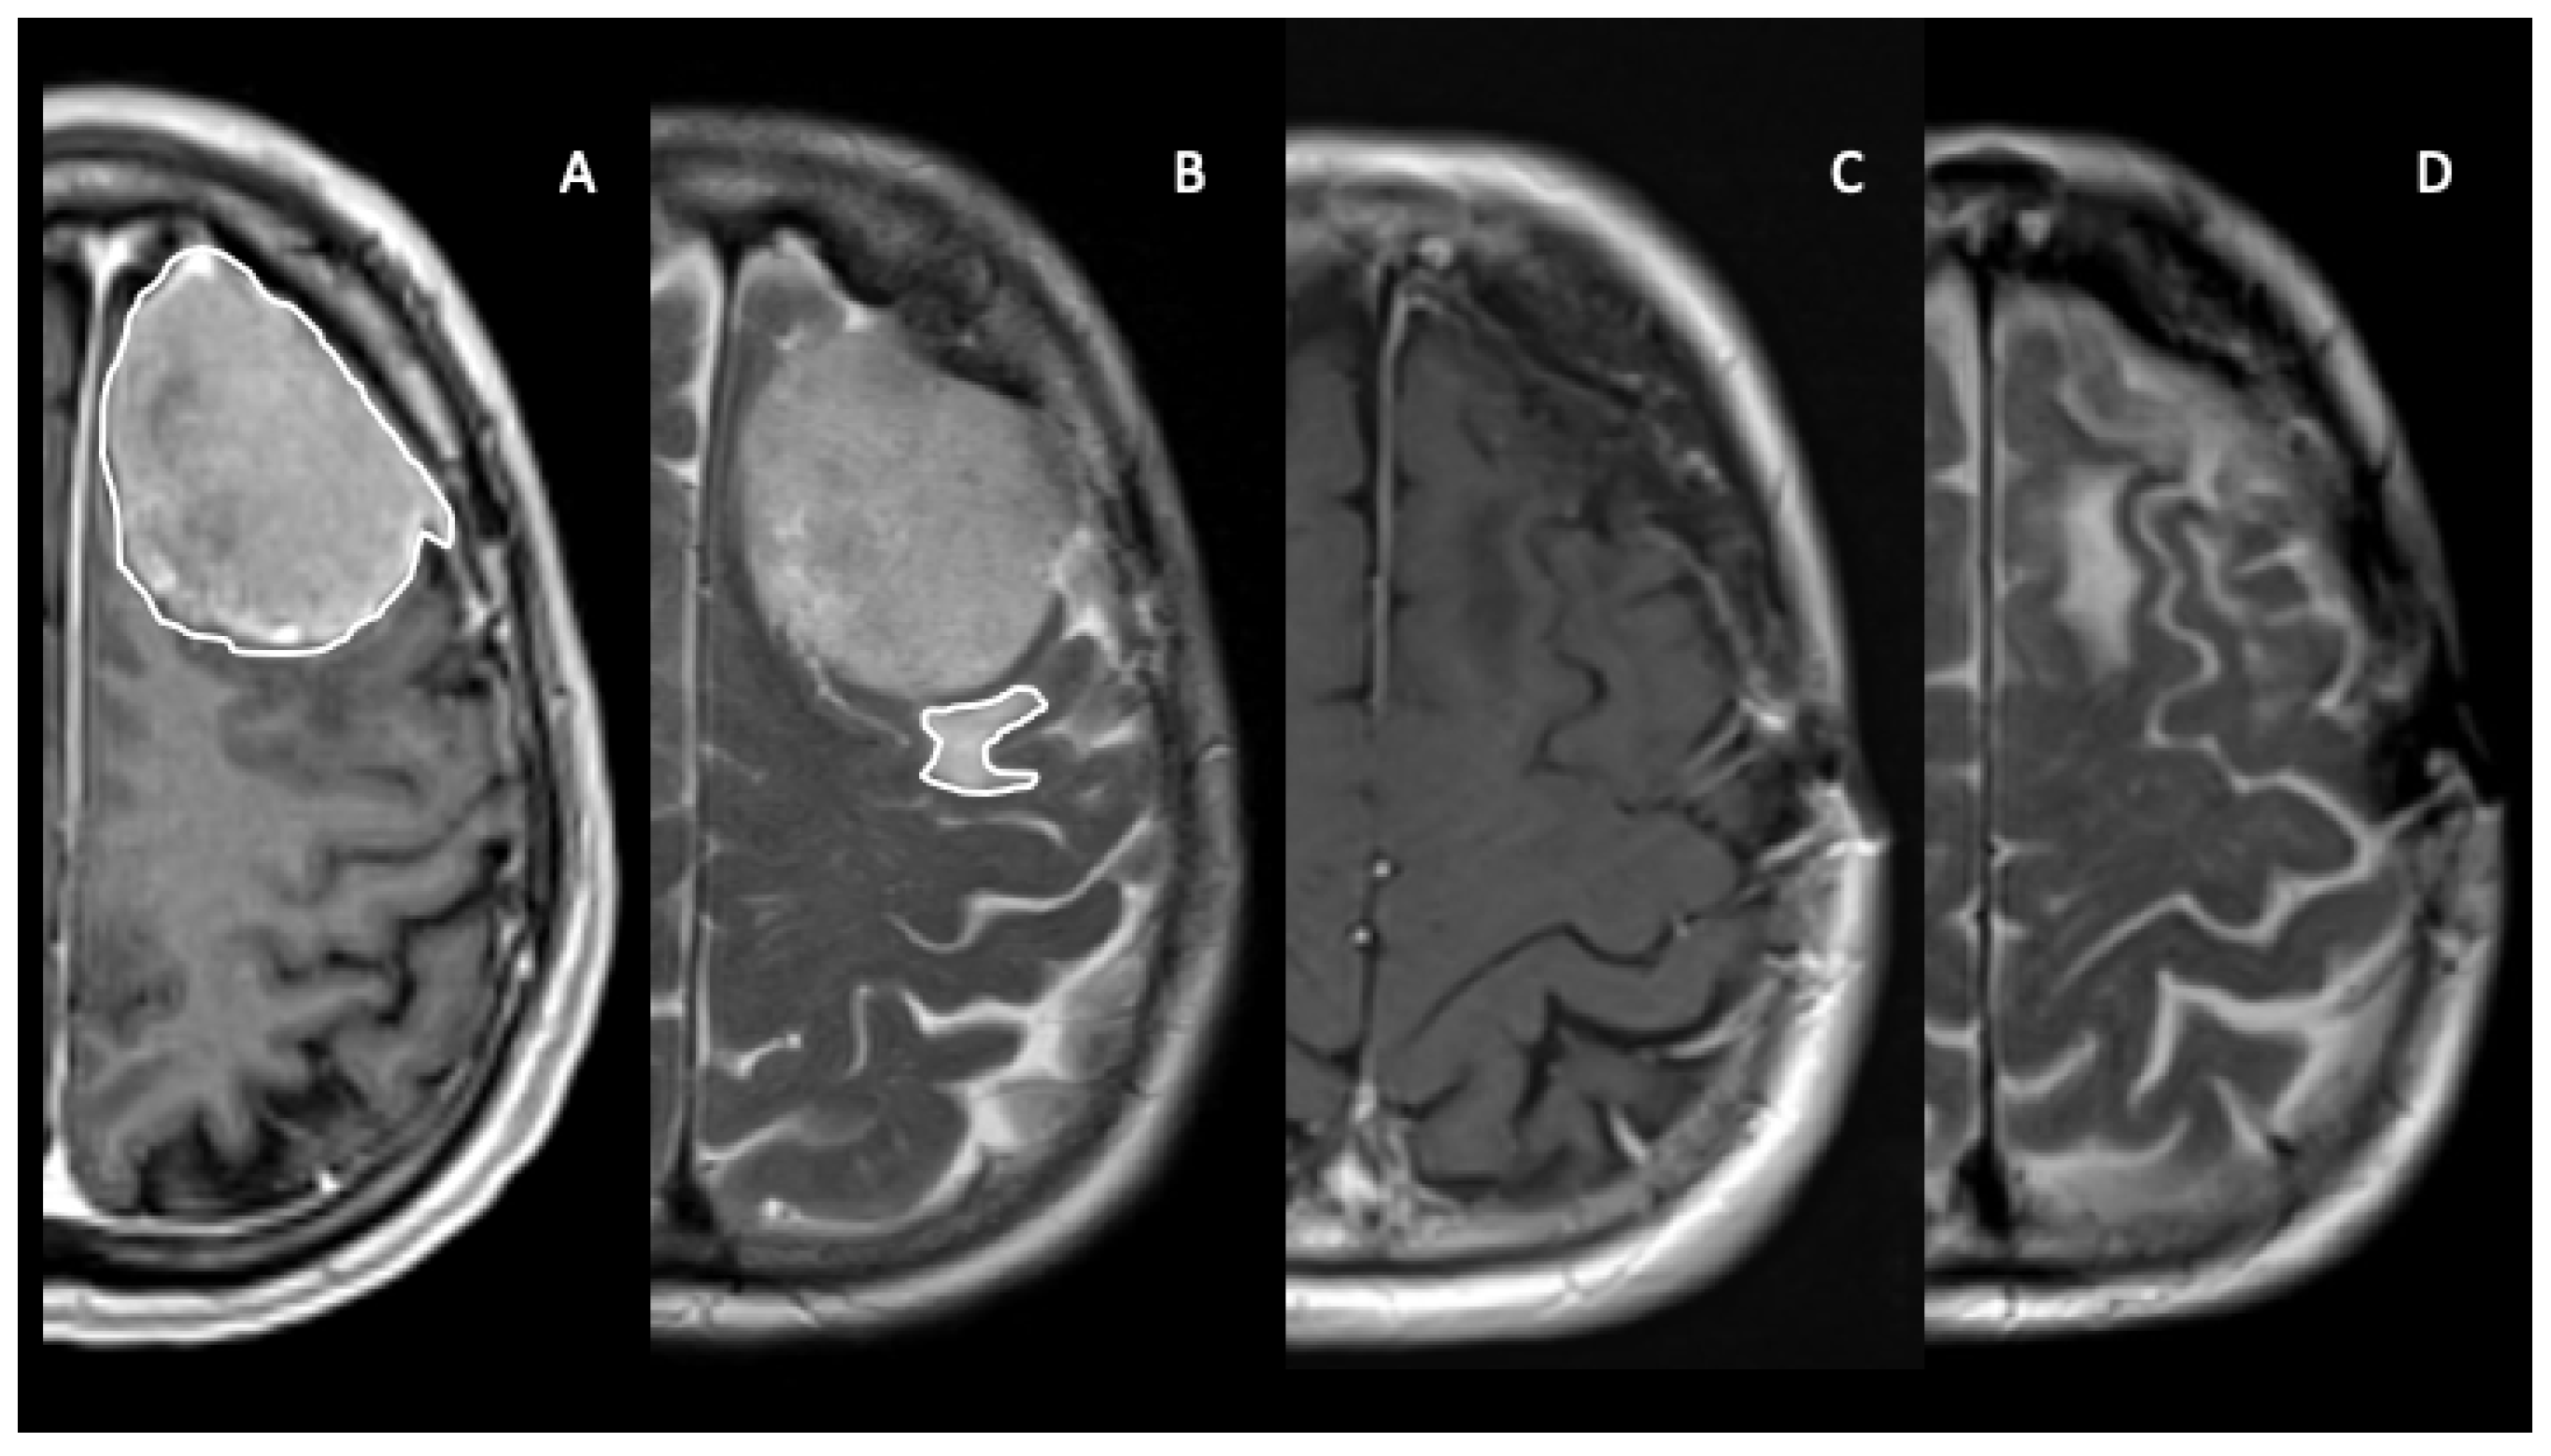

2.3. Imaging Analysis and Region of Interest (ROI)-Drawing Process

| Pre-operative tumor volume (T1-weighted MRI images–cm3) Mean Range | 20.7 1–128 |

| Pre-operative peritumoral edema volume (T2-weighted MRI images–cm3) Mean Range | 22.9 1–227 |